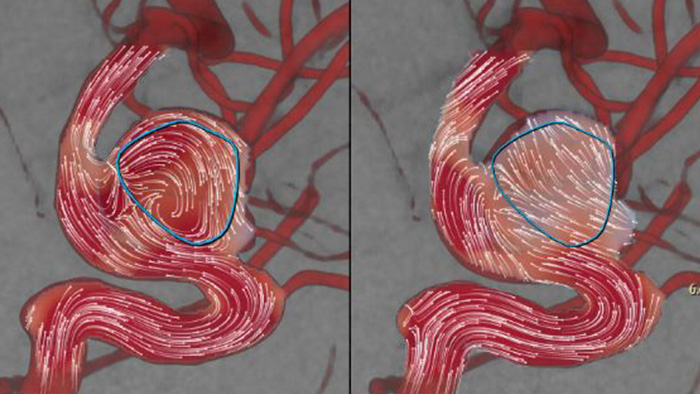

AneurysmFlow is designed to give you relevant information before and after flow diverter deployment. It visualizes and quantifies flow changes for greater confidence in procedural effectiveness.